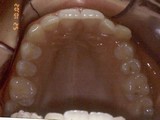

Zkřížený skus, předkus, nedostatek místa pro špičák. Léčba pomocí aparátu Hyrax a dále fixními aparáty v obou čelistech s jumping aparátem. V ústech přítomné MARA-stopy na dočasnou stabilizaci výsledku.

horní pac2       horní pac2